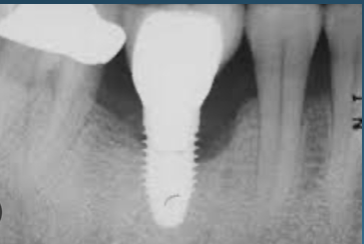

(3.) Prosthesis without access to the intaglio interface.

Figure 3

(4.) Intagilo inflammation of the soft tissue following removal of the prosthesis.

Figure 4

(5.) Prosthesis intaglio surface.

Figure 5

Several factors increasing the risk of peri-implantitis have been reported. Lack of access to the intaglio surface of the implant-supported prosthetics and poor oral hygiene of the implant is reported to increase the risk of peri-implantitis (Figure 3 through Figure 5). Concave intaglio design prevents oral hygiene access (Figure 6). Monje reported that 77.2% of the peri-implantitis cases had inadequate access for cleansability. 9 Serino and Ström found that 74% of the implants had no access to proper plaque control and highlighted the role of prosthesis design.10 Katafuchi suggested that a shallow emergence angle (EA) with a straight or concave transmucosal profile at the interproximal sites should be considered to minimize peri-implantitis risk for bone-level implant.11